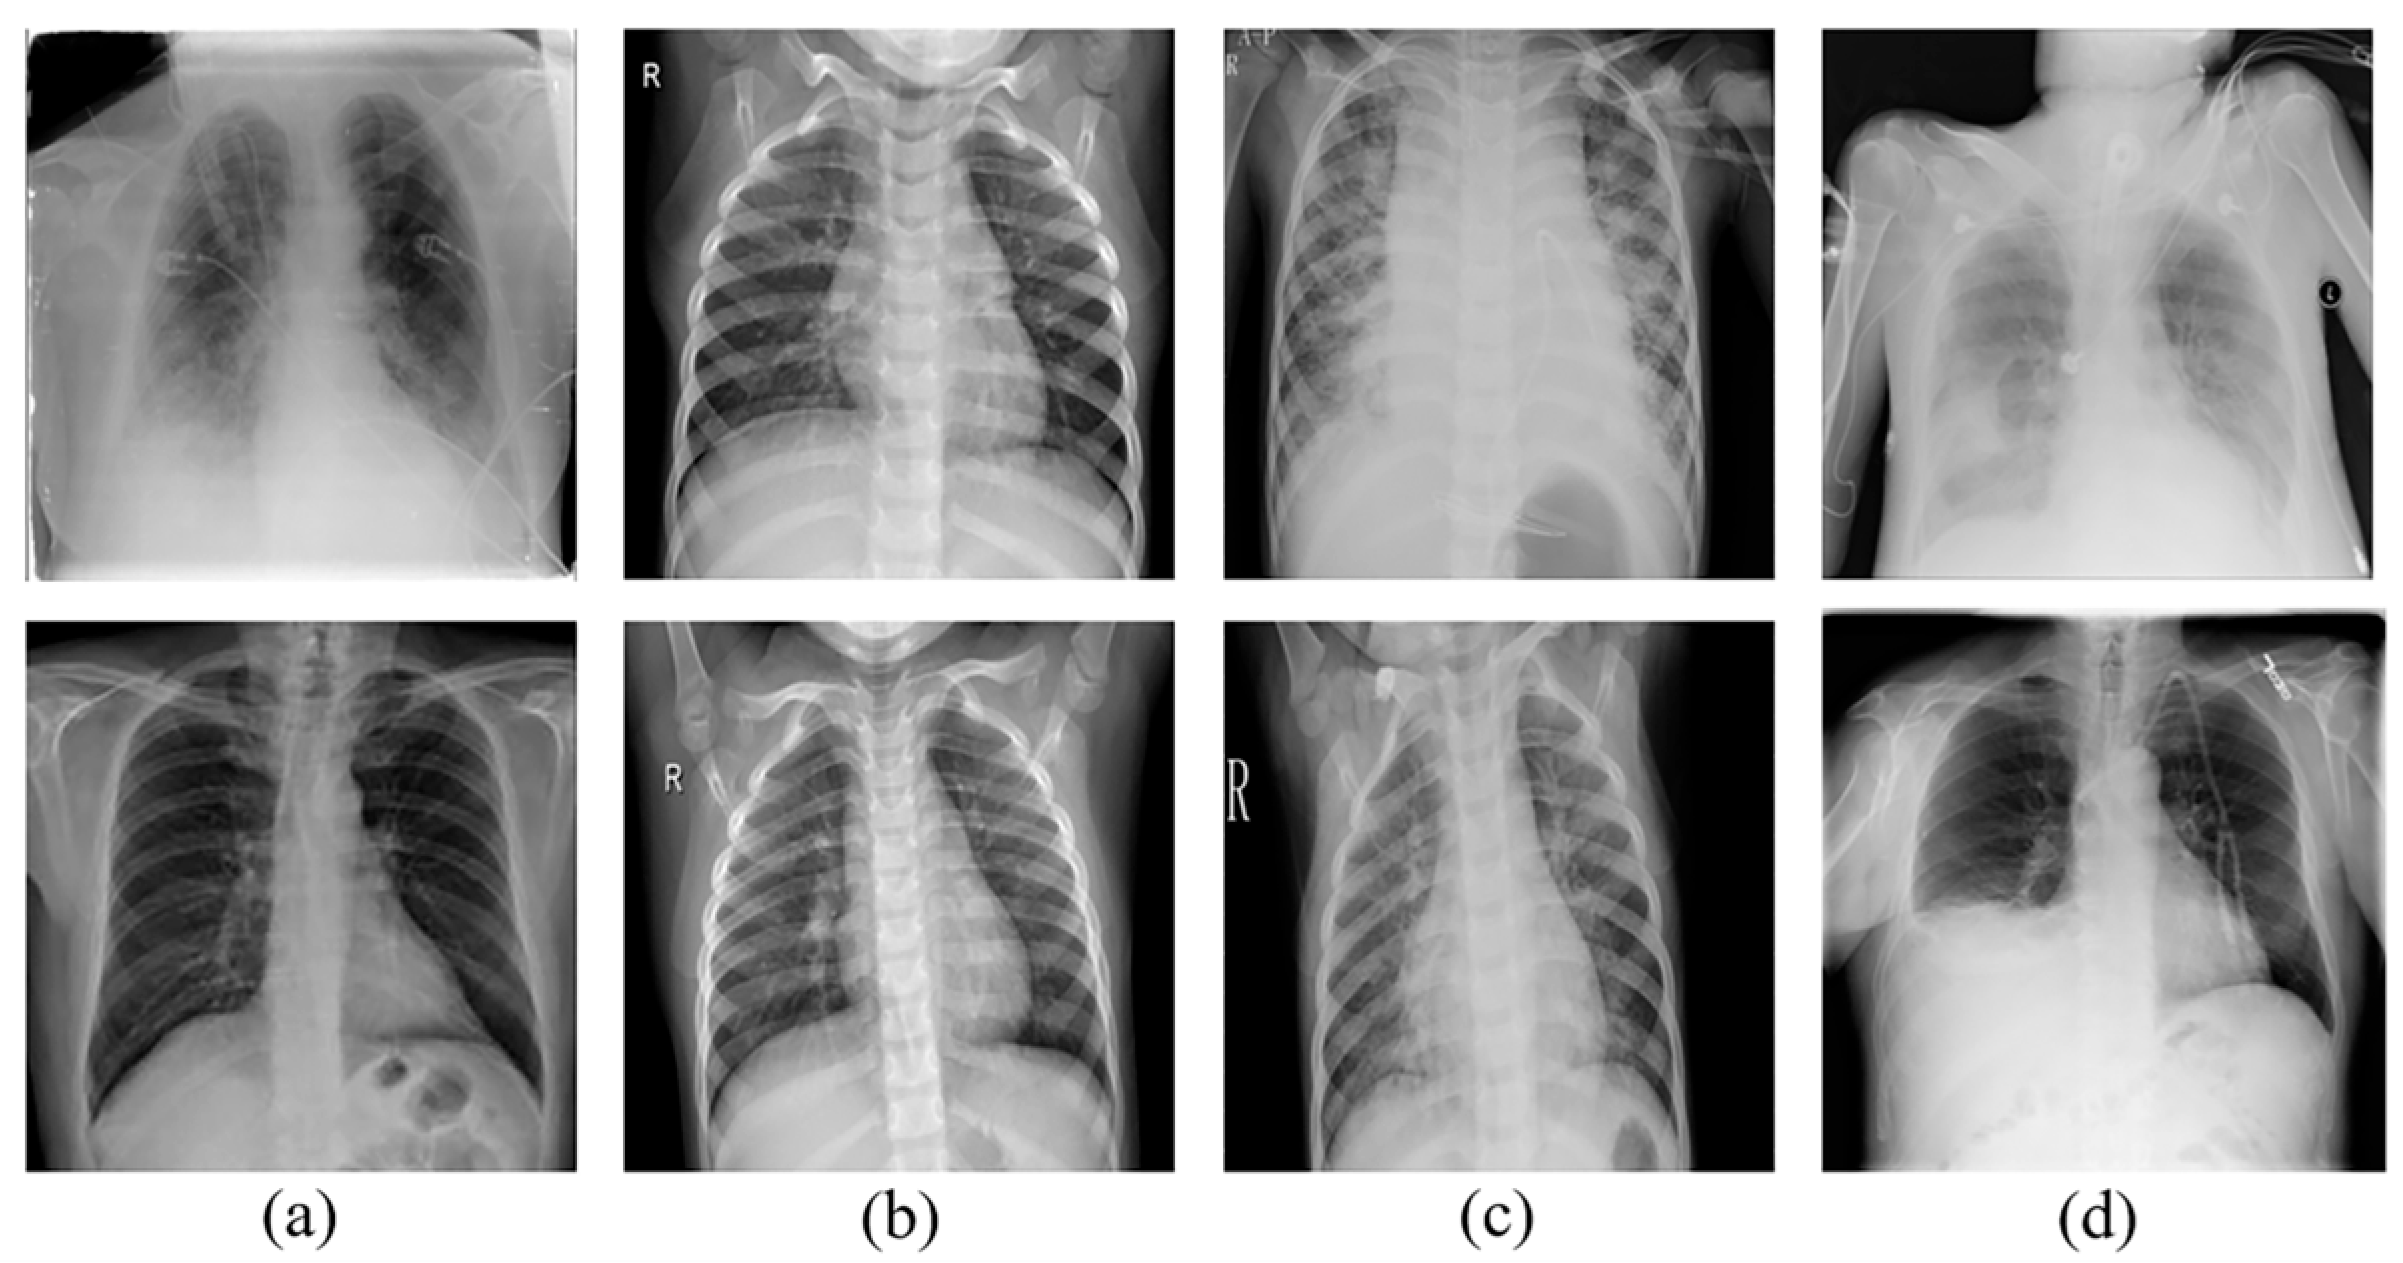

Three different types of chest radiograph datasets are used in the deep learning model proposed in this paper, which are categorized as the binary dataset [24], tertiary dataset [25], and quaternary dataset [26], dataset [24] were selected from retrospective cohorts of pediatric patients of one to five years old from Guangzhou Women and Children’s Medical Center, Guangzhou, dataset [25] was compiled from dataset [24] and various publicly available resources published on the Kaggle website, dataset [26] was created by a group of researchers from Qatar University in Doha, Qatar, and the University of Dhaka in Bangladesh, in collaboration with doctors and partners from Pakistan and Malaysia.wherein dataset [24] denotes the dataset with two types of data (normal, pneumonia), and dataset [25] categorizes the normal chest images, viral pneumonia and COVID-19. Finally, dataset [26] is more diverse as it categorizes normal chest pictures, viral pneumonia, lung opacity images (non-COVID lung infection) and COVID-19. In total, three publicly available datasets were analyzed, with a total of 13,949 normal images, 4308 COVID-19 images, 6473 viral pneumonia images, and 6012 lung opacity images (non-COVID lung infection) obtained prior to data analysis. Figure 1 provides examples.

Figure 1. (a) COVID, (b) normal, (c) viral pneumonia, (d) lung opacity.